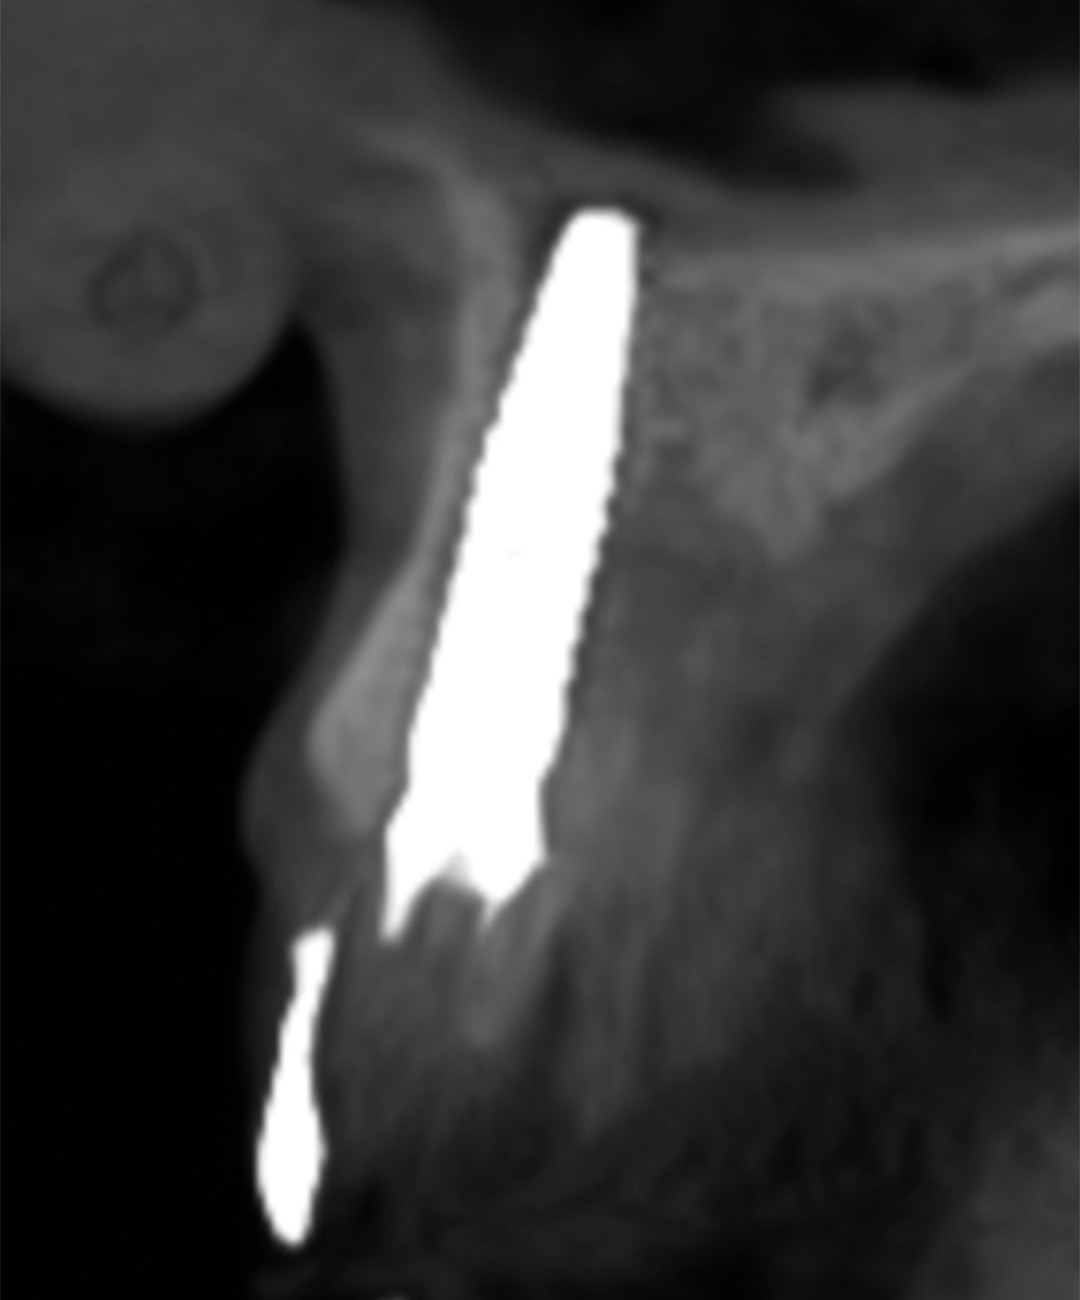

A CBCT and intraoral scans assessed the site, and coDiagnostiX® software was used to plan implant positioning and design the surgical guide virtually. The plan included immediate implant placement, filling the buccal gap with a xenograft and a soft tissue graft from the maxillary tuberosity to enhance soft tissue thickness in this high-risk aesthetic area.

An intraoral scan and a CBCT image were acquired as part of the comprehensive assessment. The images were matched using dental Blue Sky Bio software to facilitate the design of the surgical guide, using a prosthetically-driven planning approach to find the ideal 3D position of the implant. The surgical template was 3D printed and sterilised in preparation for surgery.